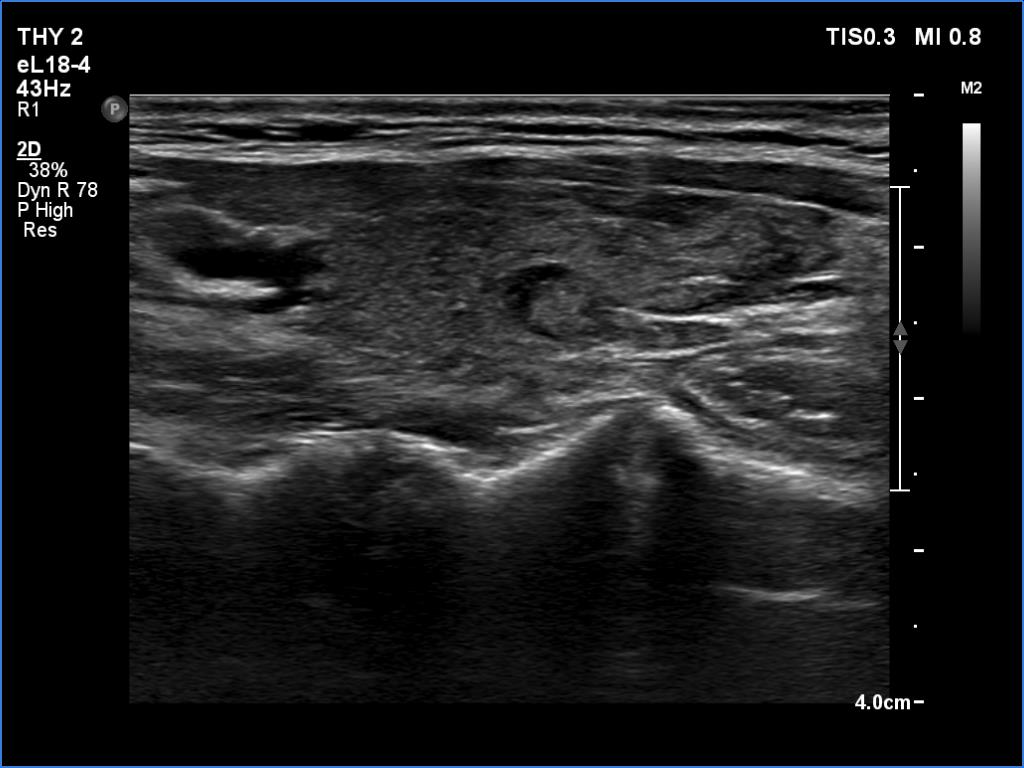

Parathyroid lesions - case 1521 (ultrasonographic picture 8)

Right lobe, longitudinal scan